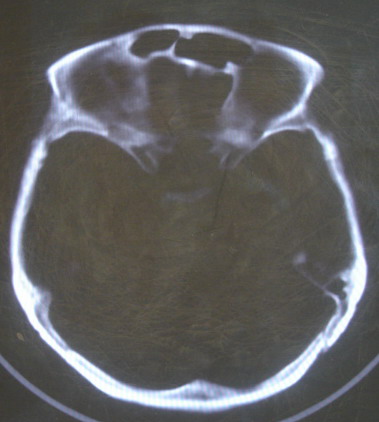

女 63岁 左额部碰伤

现有资料未见骨折表现

左枕部颅缝略增宽并轻度错位,建议结合临床,必要时复查

未见明显骨折

未见异常.

未经高分辩率处理。未见明显异常。

左额部未见明确骨折

左侧颞枕部颅缝分离骨折可疑。建议结合临床,必要时复查。

都错位了,当然是报骨折了。

左侧颞枕部颅缝分离骨折可疑。

结合临床,排除左侧颞枕部颅缝分离骨折可能。